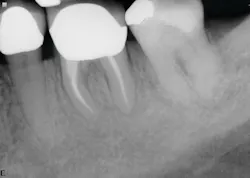

The six-month recall showed nearly complete bone and furcation healing (figure 2). There is still some attachment loss on the straight buccal, but no. 31 remains asymptomatic and in good service.